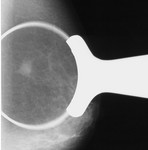

[画像診断]乳腺の硬化性腺症(sclerosing adenosis)について 2010-12-09